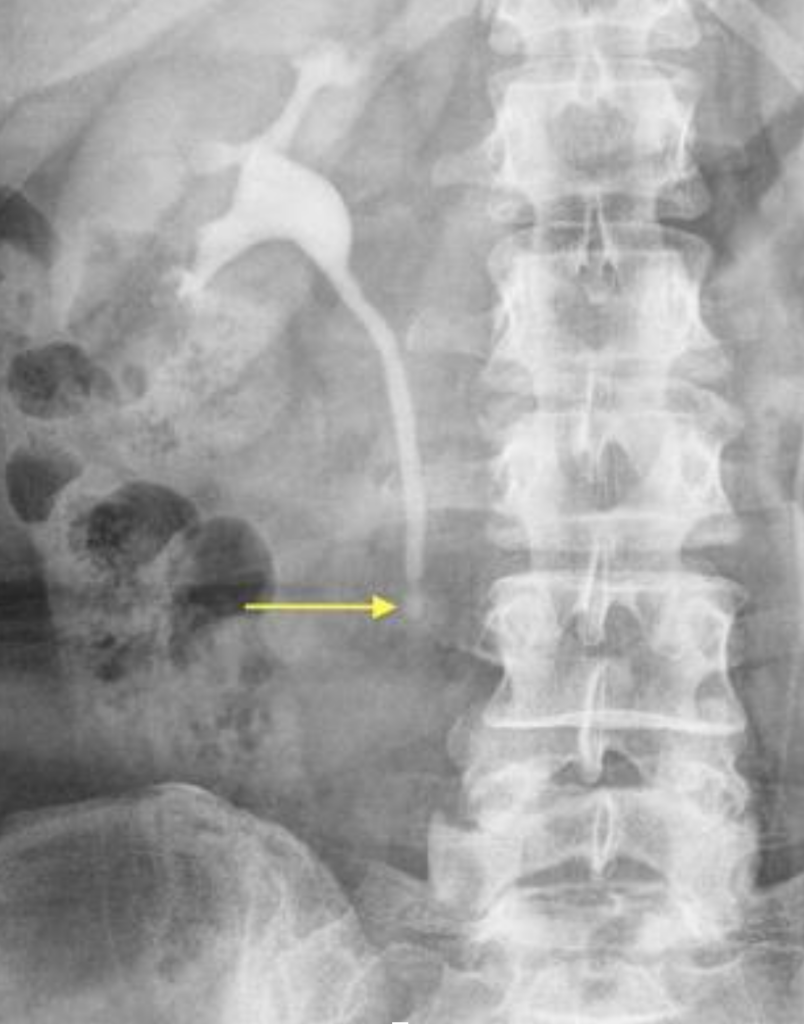

Diagnostika močových kameňov zahŕňa kombináciu hodnotenia príznakov, fyzikálneho vyšetrenia a zobrazovacích či laboratórnych testov.